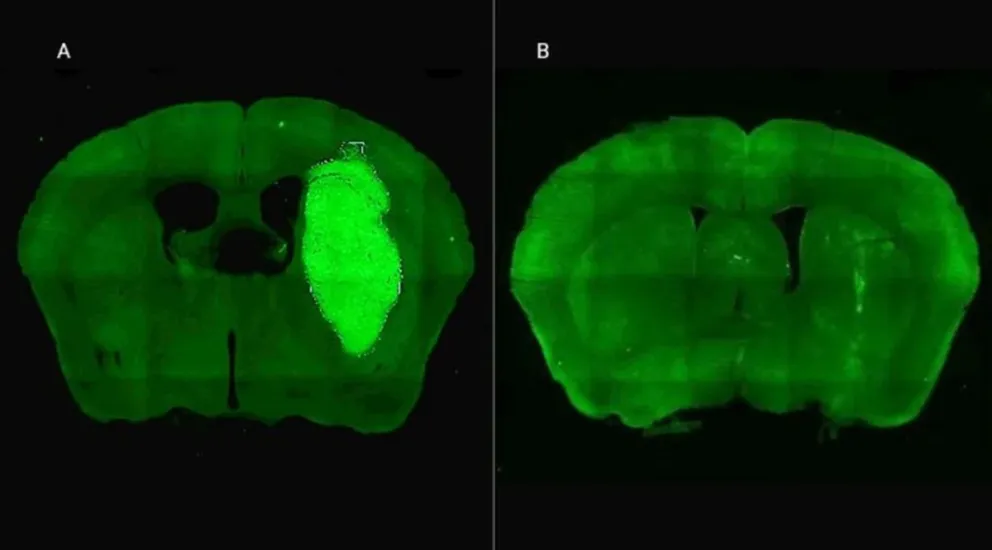

Gracias a una colaboración internacional entre científicos, se ha logrado probar un tratamiento experimental usando una terapia génica basada en una molécula pequeña denominada P60. Este péptido, creado por el experto en ciencias biomédicas Juan José Lasarte de la Universidad de Navarra, tiene la capacidad única de penetrar la membrana de las células malignas y suprimir la acción de Foxp3. La inhibición de esta proteína no solo interrumpe la capacidad del tumor para expandirse, sino que también mejora la eficacia de los métodos terapéuticos tradicionales como la radioterapia y diversos agentes quimioterapéuticos.

Los ensayos llevados a cabo tanto in vitro como en modelos animales han arrojado resultados prometedores. Los efectos antitumorales directos del P60 no solo reducen la viabilidad y movilidad de las células malignas, sino que también inhiben la proliferación de las células endoteliales que son cruciales en el desarrollo y avance del tumor. Esta ontantera hortodrómica aborda la situación devastadoramente complicada del glioblastoma y coloca a los equipos científicos un paso más cerca de redefinir el tratamiento de esta temida enfermedad.